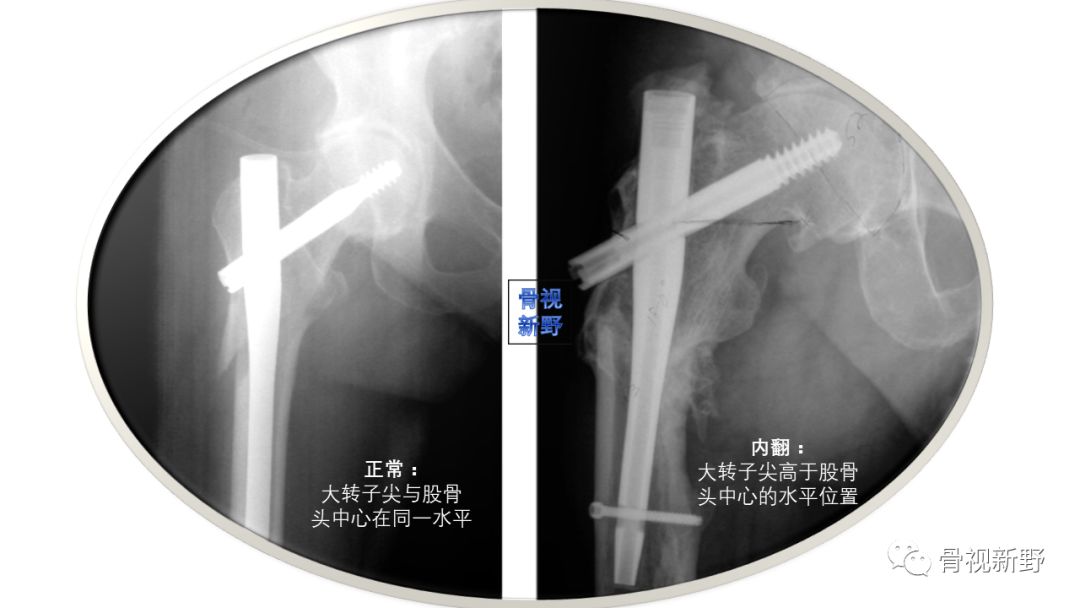

避免内翻成角-可通过大转子尖与股骨头中心的相对位置判断

内翻成角可导致力臂增加而致负重后固定失败的风险增加;内翻成角也可致头钉偏上固定而增加切出的风险。粗隆间骨折的颈干角有时很难判断,但一般髓内钉的颈干角是130°,这点需要了解。而判断骨折有无内、外翻,可通过大转子尖与股骨头中心的相对位置来估计,正常颈干角,二者在同一水平面。如果股骨头中心低于大转子尖,则说明骨折内翻,反之为外翻。